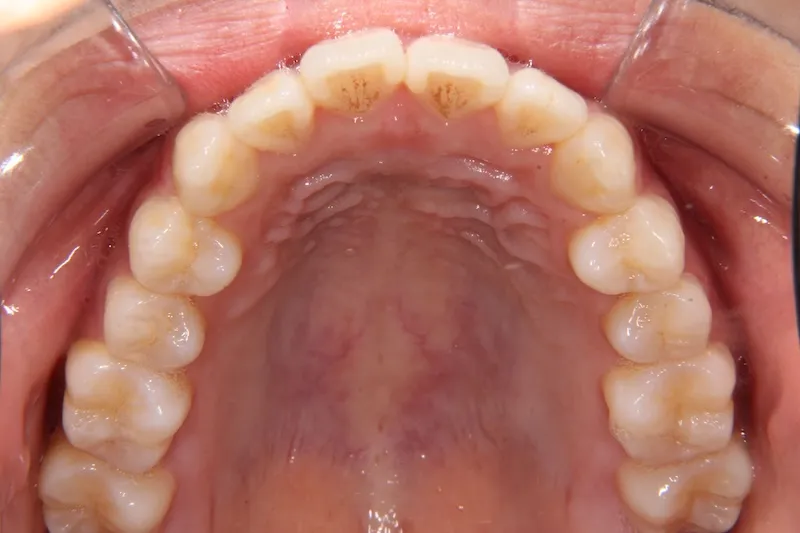

初診時

初診時年齢 19~29歳 (女性) 主訴 前歯で物が噛みちぎれない

診断名 開咬・上顎前突 装置名

状態 出っ歯(口元が出ている/上顎前突)

前歯で噛めない(開咬/オープンバイト)

前歯で物が噛みちぎれないを主訴に来院された患者様です。

非抜歯で、オリジナルリンガルアーチと歯科矯正用アンカースクリューを用いて治療しました。

治療回数15回、1年の治療期間で矯正治療を終了しました。

主訴が改善され、ご満足頂きました。